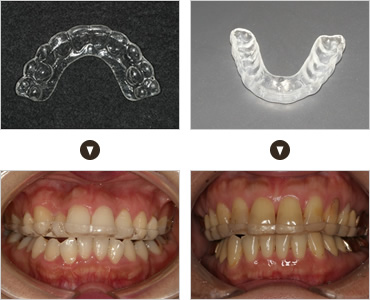

- NIGHT GUARD

- ナイトガードでの治療

- ナイトガードをすることで、自分の咬む力で歯が破壊されていくことを少しでも遅らせ、

歯の寿命を延ばすことができるかもしれません。

歯を失う原因はむし歯や歯周病だけではありません。歯並びや歯ぎしりによる自分自身の咬む力によっても歯は、ダメージを受け何らかの支障をきたすようになります。虫歯や歯周病の治療だけでなく、咬み合わせや歯ぎしりの治療もしていくことで、歯の寿命を延ばすことができ、年をとっても自分の歯でしっかり咬んで食事をすることができるでしょう。心当たりのある方は、ナイトガードで歯を守りましょう!!